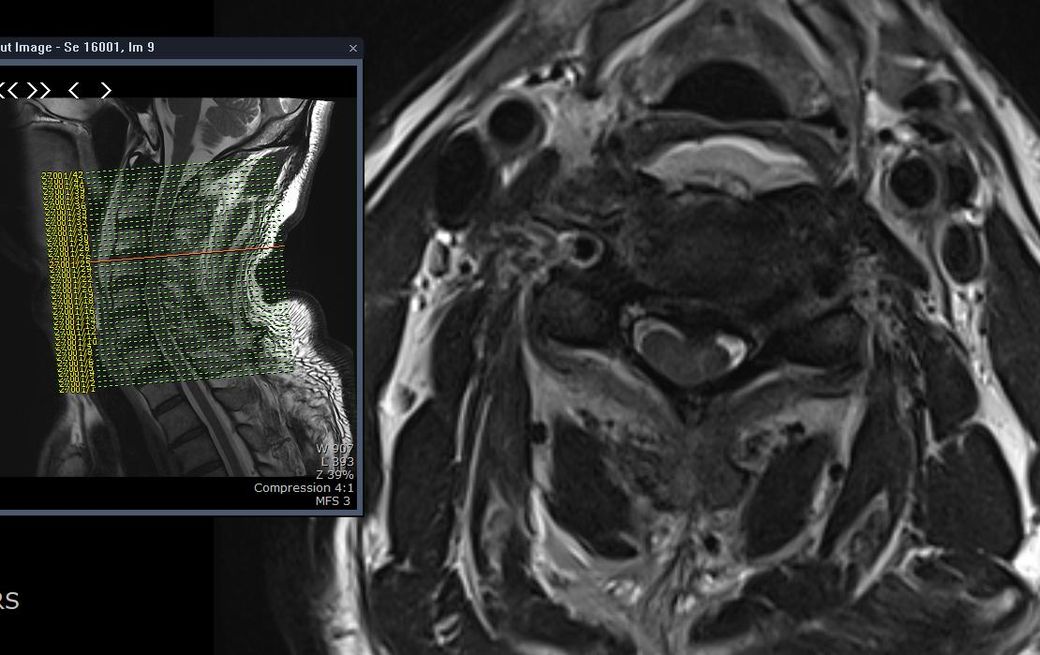

양측 상지의 근력저하가 심하고 하지는 근력저하가 없습니다.

척추 중심관으로 골절은 없는데 디스크 손상에 의한 척수손상에서 수술이 꼭 필요한가요?

근력의 저하가 있고 해당 병변이 원인이라면

네 수술의 필요성이 있을 것 같습니다.